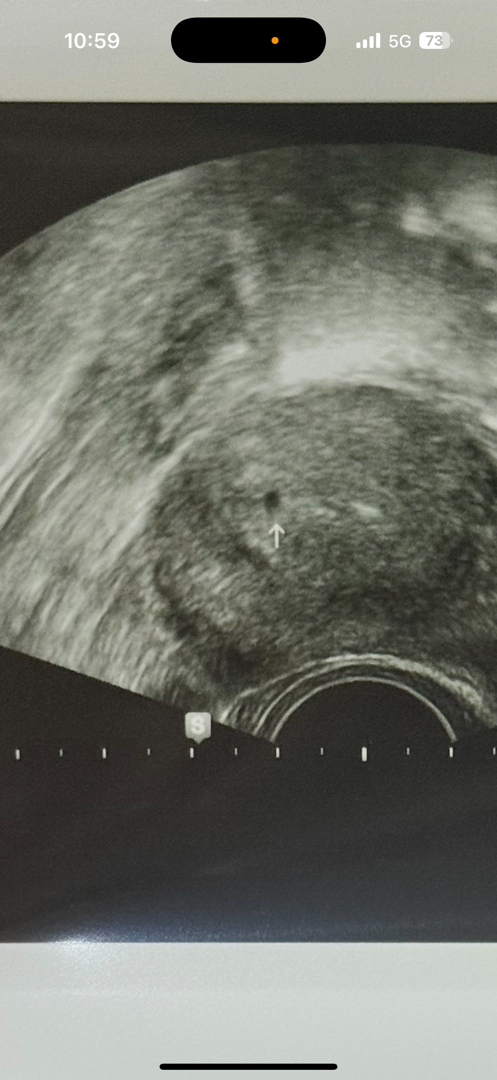

아기집

아기집 맞아요

아기집 맞아요~!!